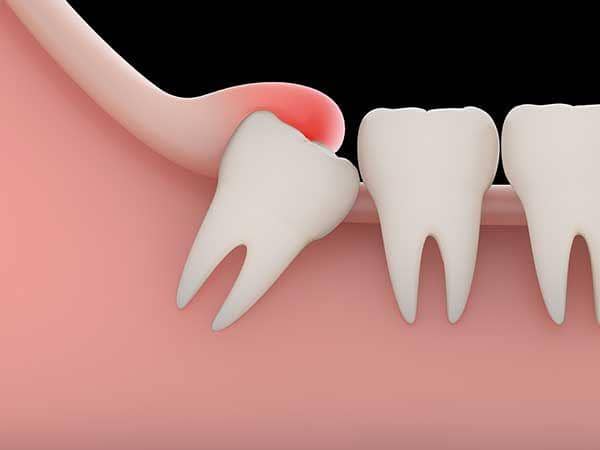

Apalagi, ketika wisdom teeth tumbuh tidak sejajar atau tak beraturan. Gigi ini dapat tumbuh miring dan tumbuhnya gigi ini dapat memengaruhi gigi lain, bentuk rahang hingga sistem saraf. Selain itu, gusi juga akan terasa sakit dan berdenyut ketika gigi ini memaksa untuk tumbuh.

Biasanya, wisdom teeth tumbuh kurang sempurna. Tak semua bagian gigi tumbuh ke permukaan, sisanya lebih banyak tertanam di gusi. Ini memungkinkan munculnya bakteri di sekitar gigi dan menyebabkan infeksi serta bengkak, jelas laman Web MD.